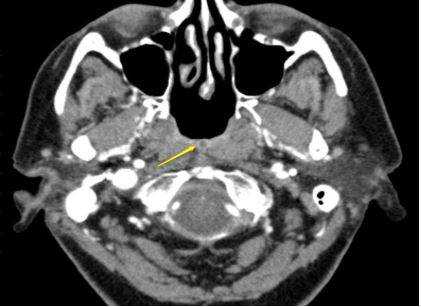

Слева — КТ-снимок одонтогенной кисты в верхнечелюстном синусе, справа — МР-фото образования (указано стрелкой) в гайморовой пазухе

Компьютерная и магнитно-резонансная томография отличаются по своей сути. КТ подразумевает воздействие на организм рентгеном. Изображение формируется в результате улавливания аппаратом Х-лучей, прошедших сквозь рассматриваемую анатомическую область. Плотные структуры организма в большей степени поглощают излучение, поэтому на снимках выглядят светлыми. КТ незаменима для исследования костей. Мягкие ткани лучше отображаются после введения контраста на основе йода. Компьютерная томография занимает несколько минут, поэтому востребована в экстренной медицине.

Магнитно-резонансное изображение измененной лобной пазухи

В основе МРТ лежит воздействие на организм магнитного поля, под влиянием которого меняется траектория движения протонов водорода. Томограф улавливает импульсы и преобразует их в картинку.

Водород есть в тканях, насыщенных жидкостью, поэтому МРТ детально показывает рыхлые структуры организма. Оборудование мощностью от 1,5 Тл дает подробные снимки изучаемой области. Изображения производят послойно, с шагом от 1-2 мм. Это позволяет выявлять патологические очаги размером от 3 мм.